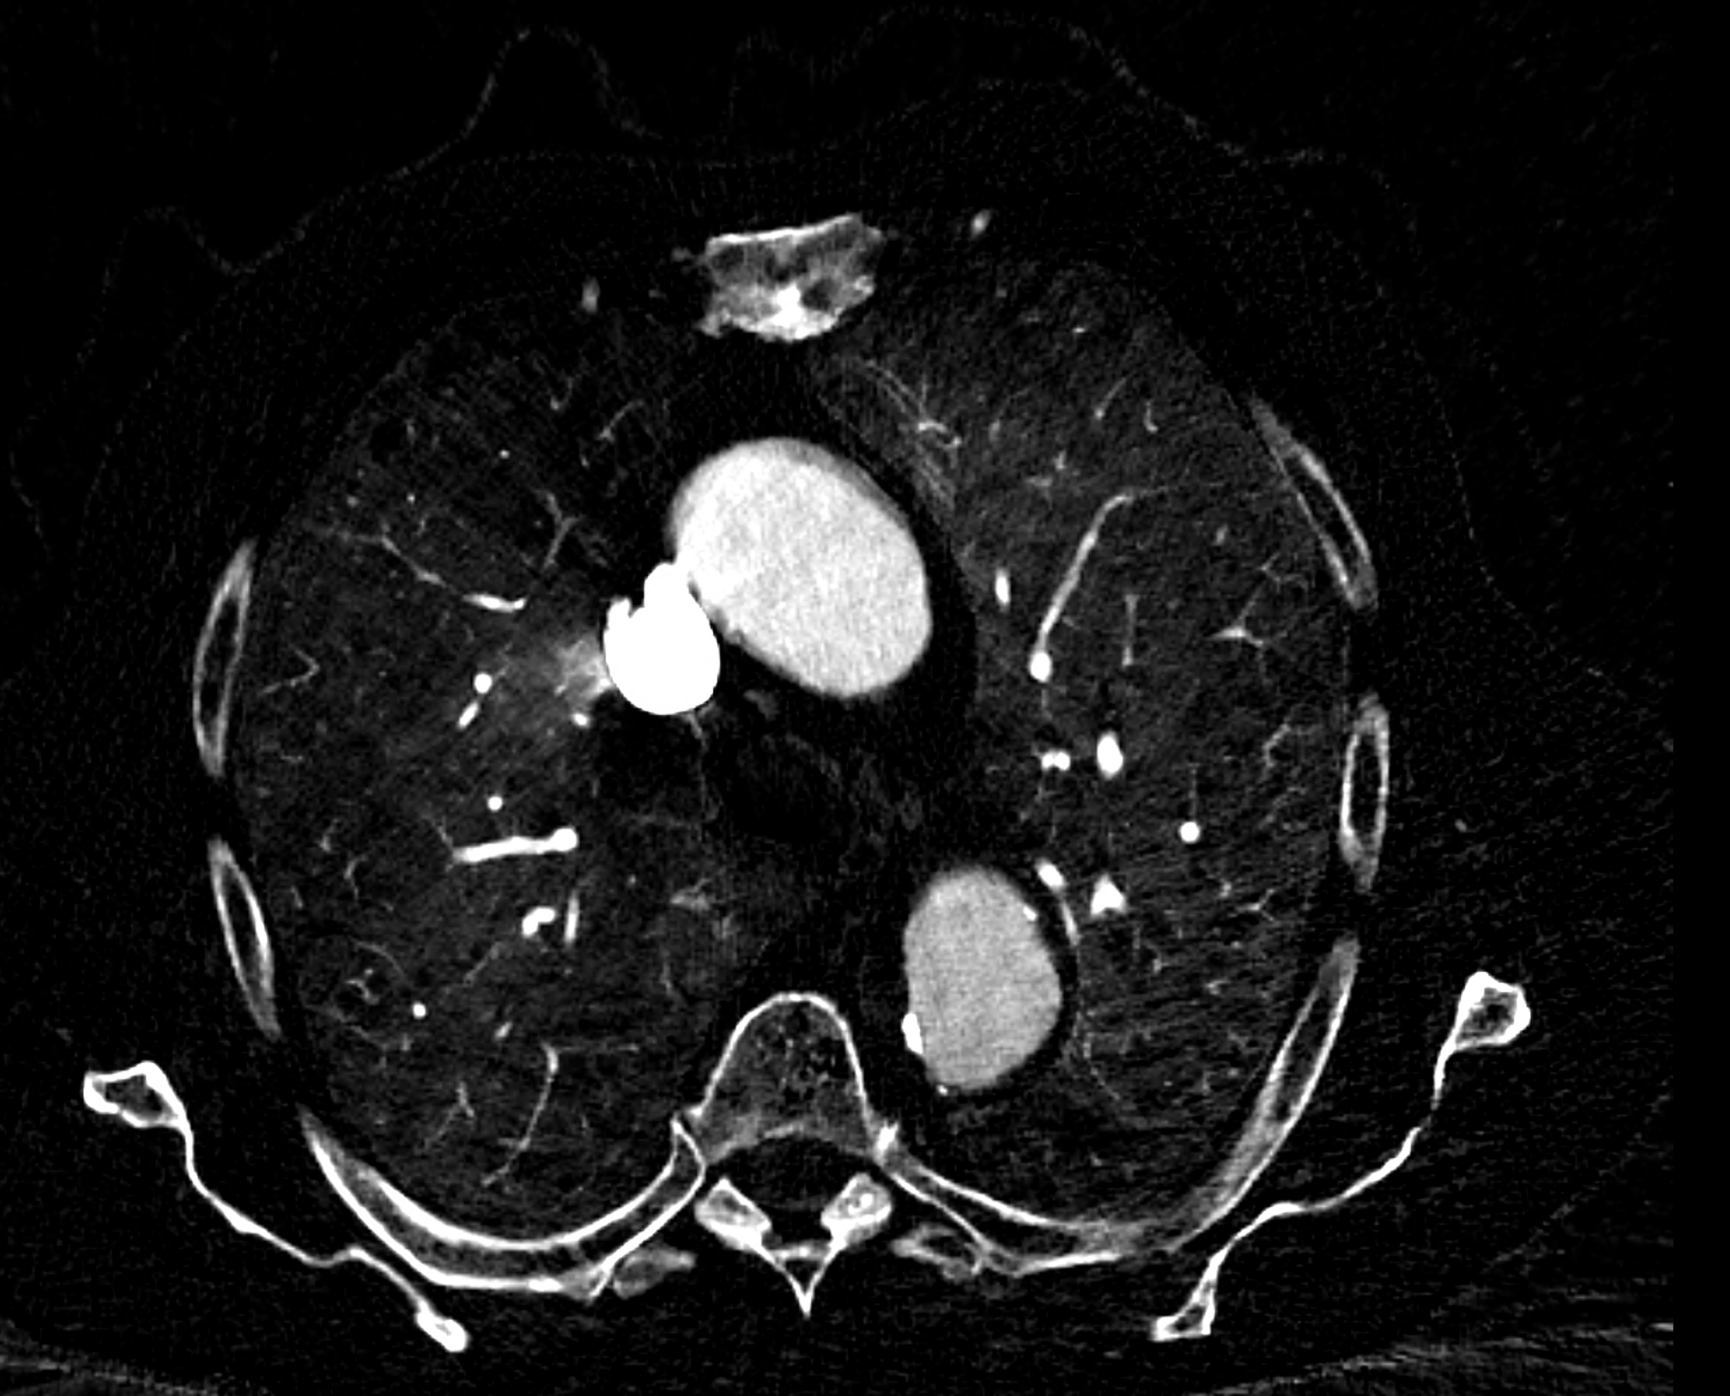

in patient chest pain, negative ECG but with elevated D-dimers was performed CTA of the chest to exclude highly suspected pulmonary embolism. No pulmonary embolism was see, but the pathology of the aortic arch and descending thoracic atorta. The images were consistent with aortic intramural hematoma type B according to the Stanford classification with incipient transformation in dissection – behind the subclavian artery, it is clear that the contrast agent is flowing into the intramural hematoma. Differentiation from wall thrombosis is facilitated by the presence of calcification in the detached intima, which is most clearly visible on virtual non-contrast imaging. The intramural hematoma itself exhibits different properties in terms of X-ray absorption. Coagulated blood is visible at the apex of the aortic arch, where it closely adjoins the area that is perfused and filled with contrast medium. There are other smaller areas filled with contrast medium at the sites of the intercostal arteries. These areas are secondary sites where the original intramural hematoma is channeled during its transformation into a classic aortic dissection.

Virtual non-contrast images help to distinguish between the intima and thus in the differential diagnosis of intramural hematoma versus wall thrombosis. Signs of fresh coagulated blood in IMH indicate bleeding into the aortic wall from the vasa vasorum. In contrast, monoenergetic images with lower energies of 40-55 keV highlight areas of intramural hematoma with active blood flow.

comparison of the the images 60, keV monoenergetic, virtual non-contrast (VNC), and iodine map images. The repercussion starts in the proximal tear of the intimate (the first three images), calcification in the intimate (next three images), tera at the level of the arising intercostal artery (last three images)

comparison of the sagittal aortic MPR in 40, 60, 140 and 190 keV monoenergetic images

comparison of the perpendicular planes to sagittal aortic MPR in 40, 60, 140 and 190 keV monoenergetic images